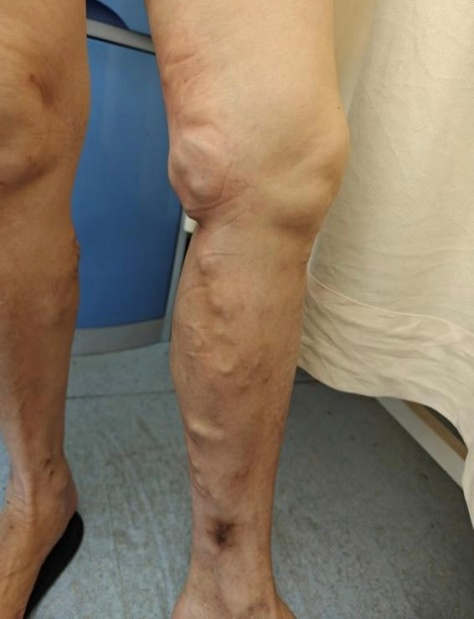

想象一下,我們的血管就像一條條河流,負(fù)責(zé)把血液從腳送回心臟。但有時(shí)候,這些“河流”會(huì)變得蜿蜒曲折,甚至在某些地方變得膨脹,導(dǎo)致血液在腿部滯留。這就像是排水管被堵住了,水流積起來(lái)排不出去,我們腿部那些外觀(guān)類(lèi)似于蚯蚓的血管,就是靜脈曲張。

曲張的血管:腿部的血管顏色看起來(lái)很顯眼,彎彎曲曲,就像“蚯蚓”一樣。